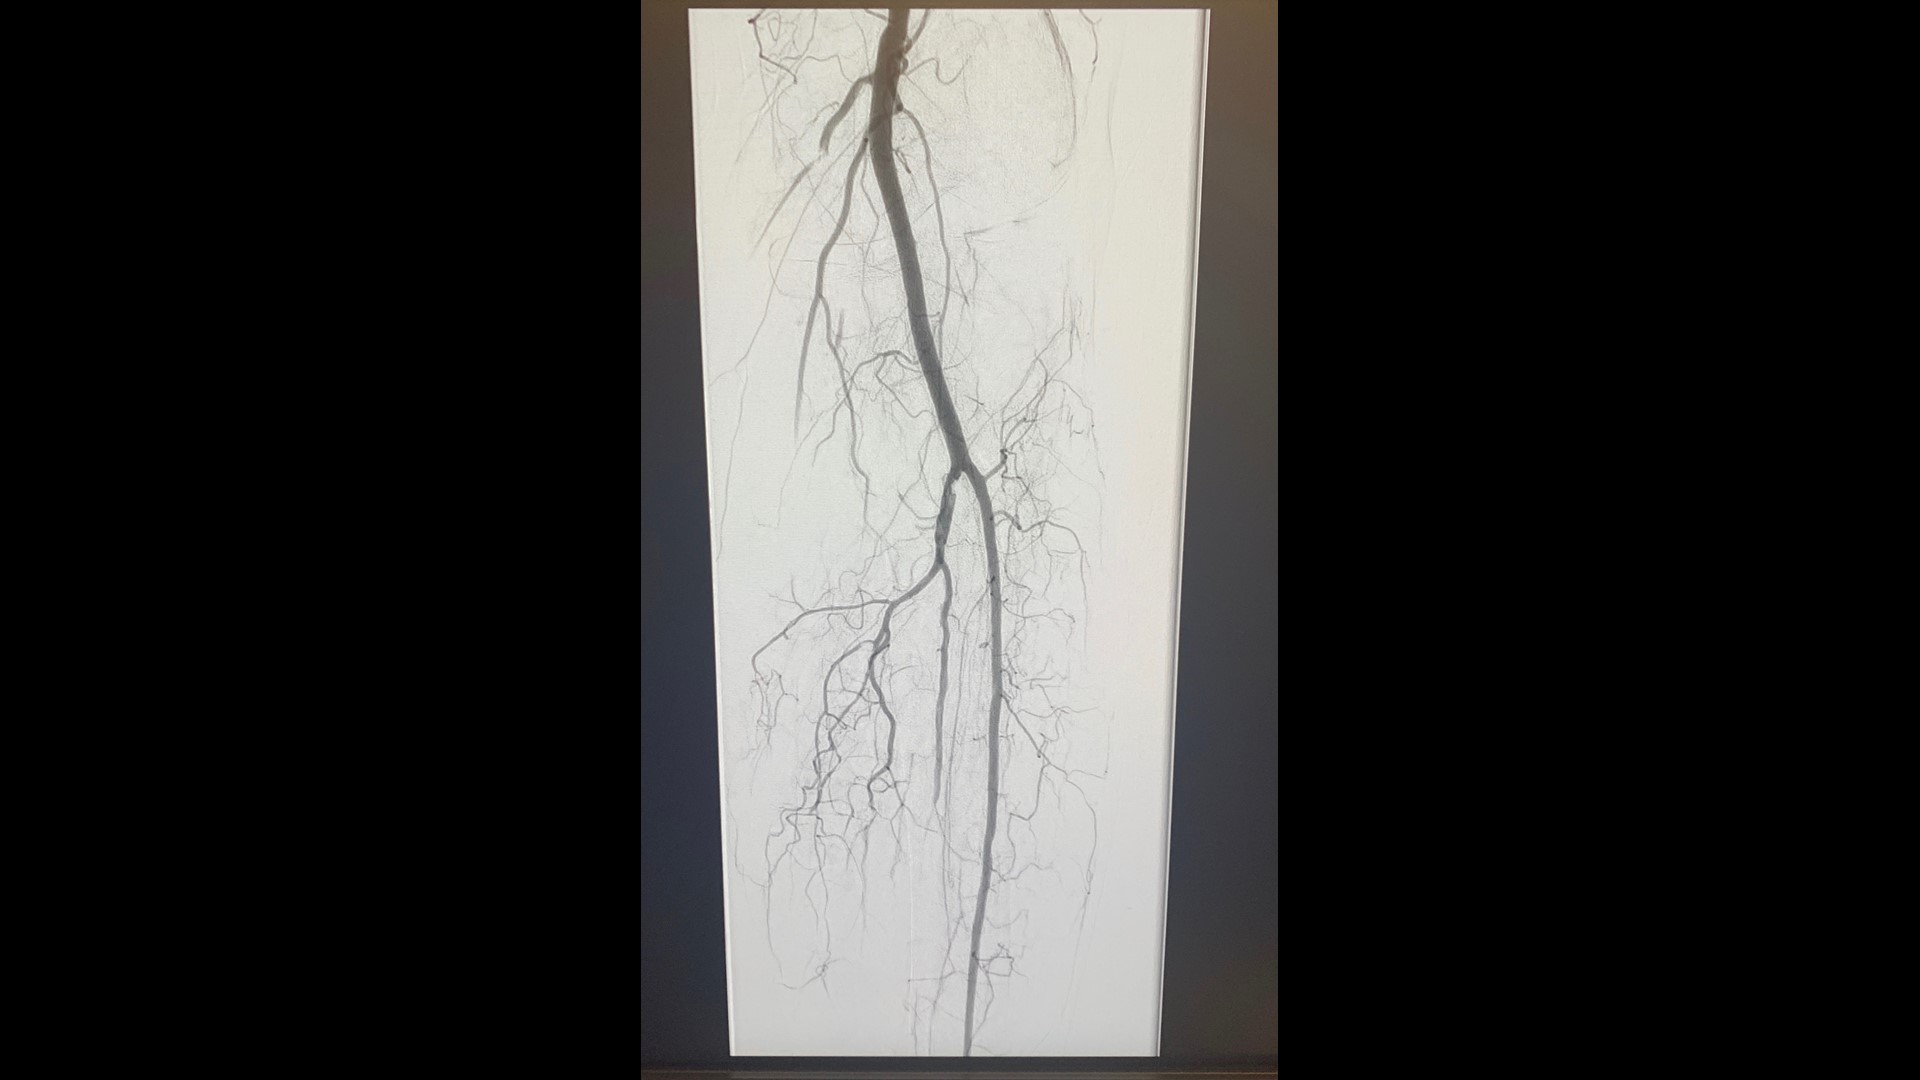

Vascular surgeon says she sees COVID19 patients with blood clots After Having Covid Can You Get Blood Clots And your risk for clots stays elevated for a month after. “when you, say, fall and skin your knee, it turns your immune system on, and one of. After Having Covid Can You Get Blood Clots.

Covid Creates Higher Risk for Blood Clots Than Vaccines Do The New York Times After Having Covid Can You Get Blood Clots And your risk for clots stays elevated for a month after. “when you, say, fall and skin your knee, it turns your immune system on, and one of. After Having Covid Can You Get Blood Clots.

What to Know About Blood Clots and COVID19 After Having Covid Can You Get Blood Clots And your risk for clots stays elevated for a month after. “when you, say, fall and skin your knee, it turns your immune system on, and one of. After Having Covid Can You Get Blood Clots.